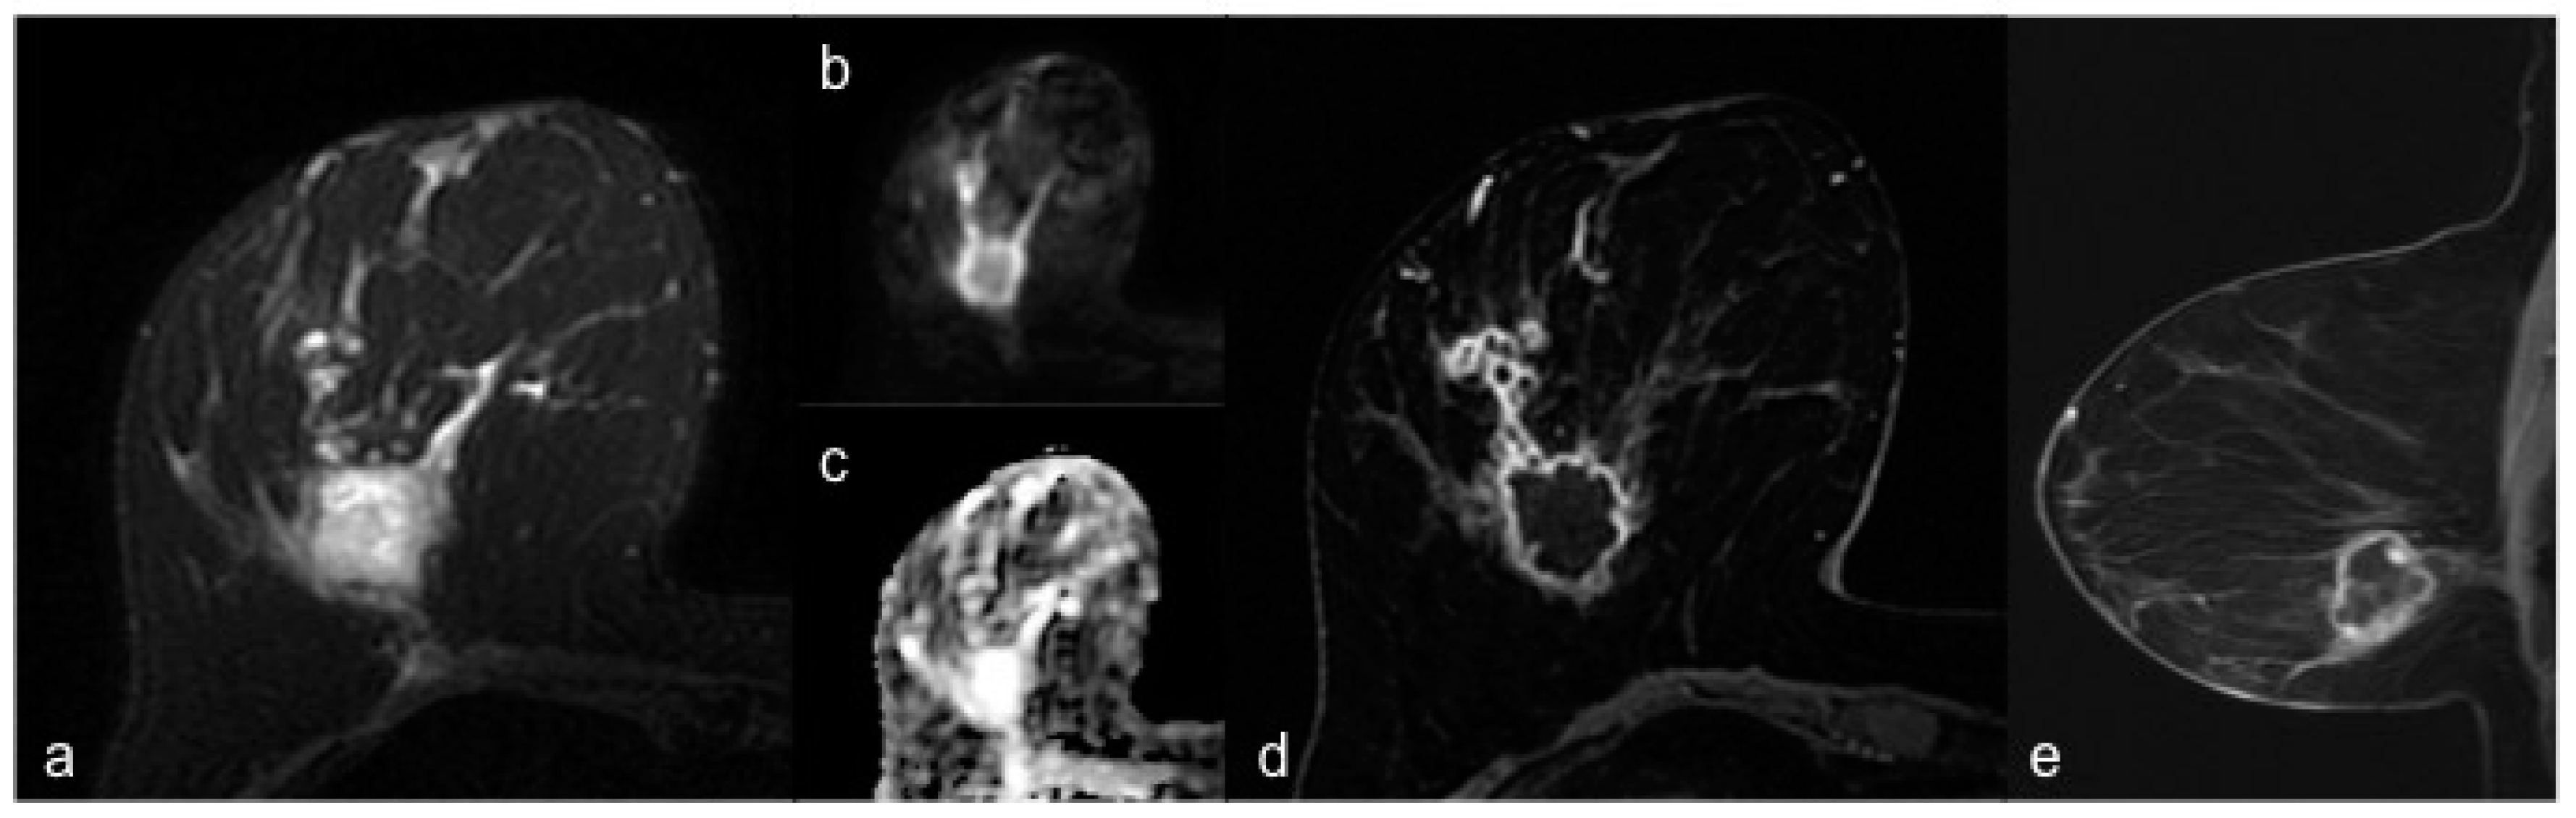

3. Results